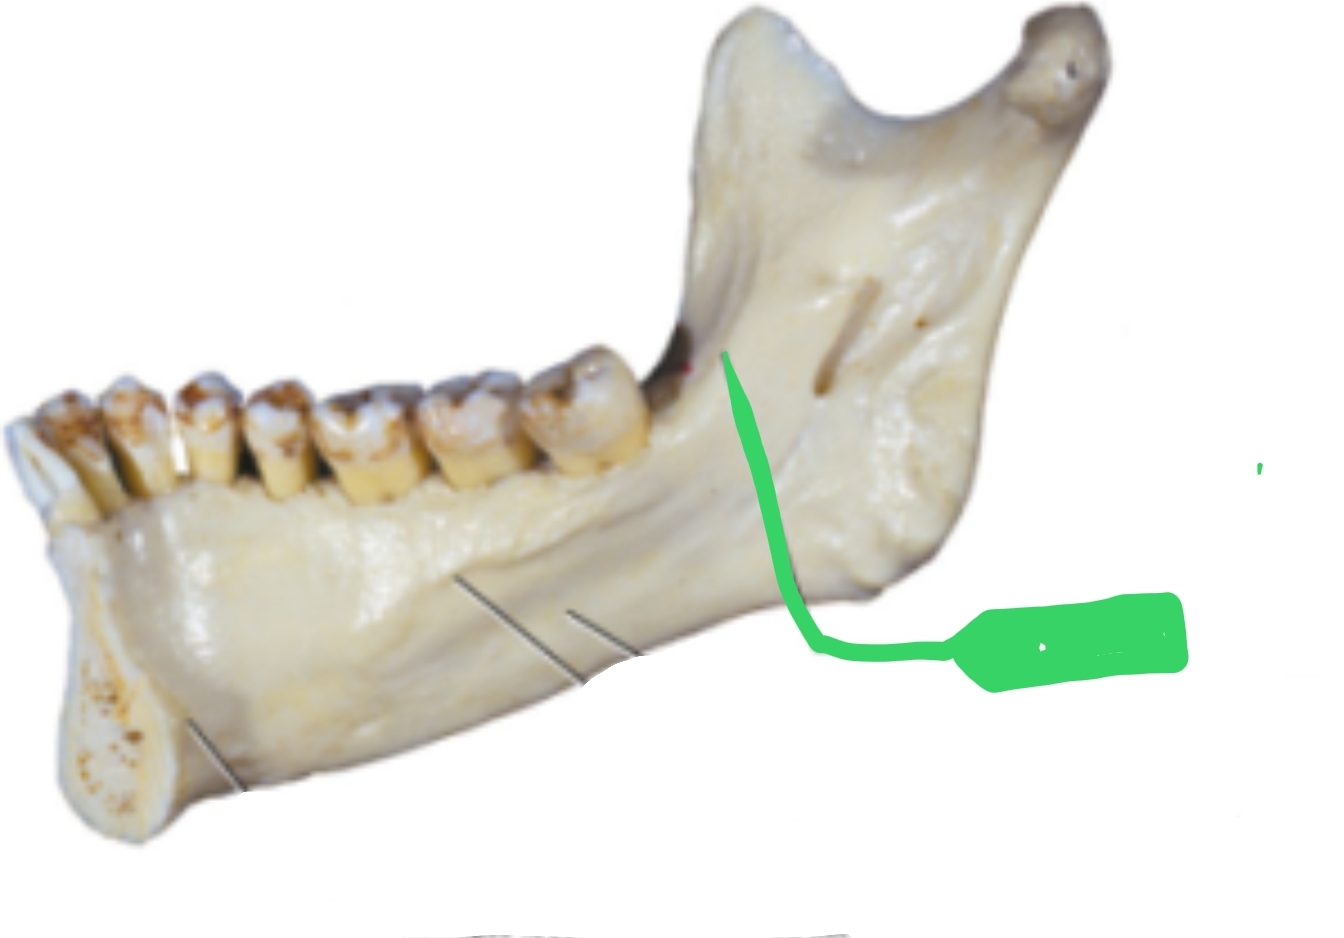

The _________(green) is located on inner surface of ramus; elevation of bone which protects entrance of _________(pink) (opening)

Lingula, mandibular foramen